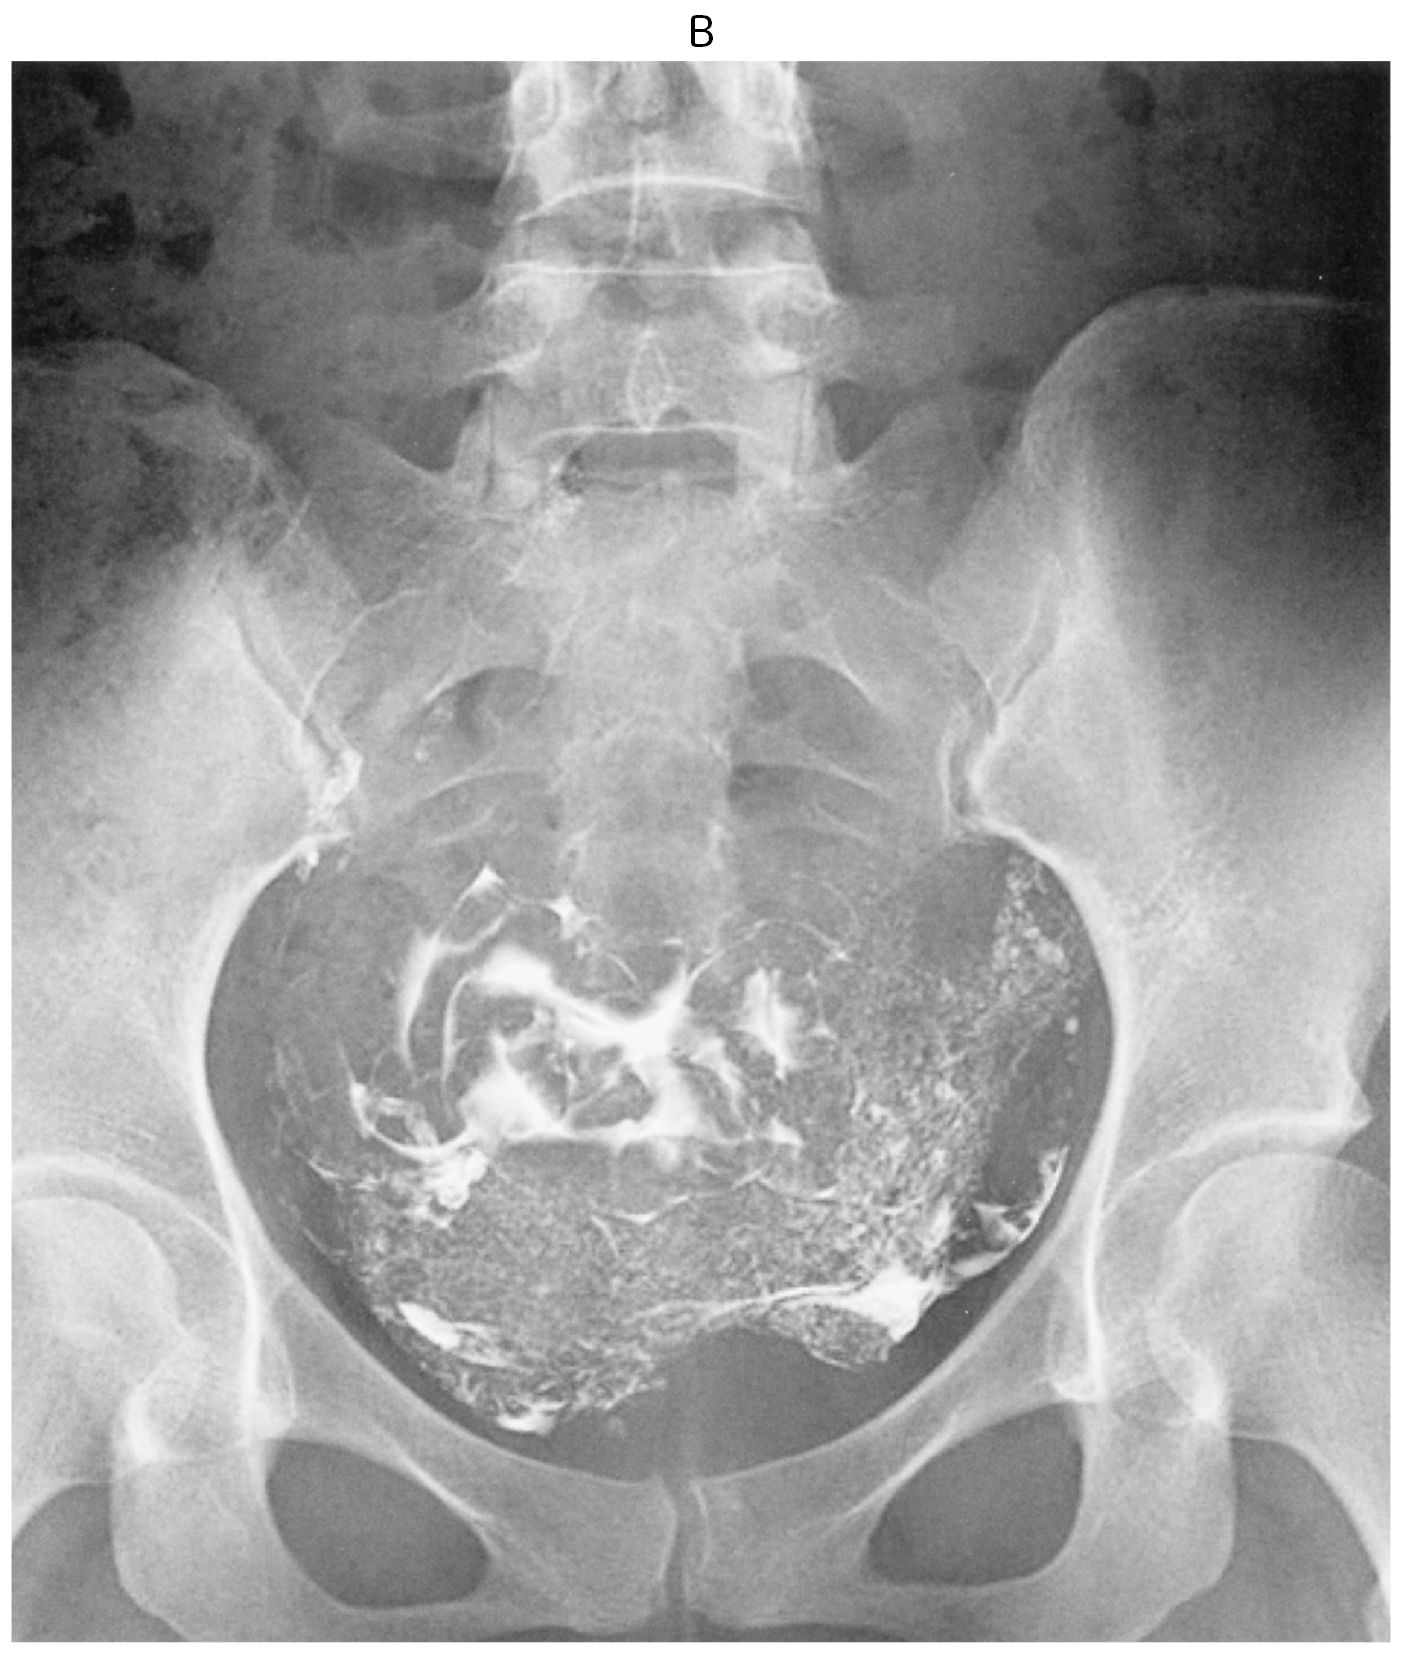

35歳の女性(0妊0産)。挙児を希望して来院した。1年前に結婚してから避妊はしておらず,1か月に1回程度の性交があり,軽度の性交痛がある。初経12歳。月経周期は30~40日型,整,持続6日間。月経痛は認めない。基礎体温は2相性である。身長162cm,体重55kg。内診で子宮は正常大で,両側付属器は触知しない。血液生化学所見(月経3日目):LH 5.2mIU/mL(基準1.8~7.6),FSH 8.2mIU/mL(基準5.2~14.4),プロラクチン〈PRL〉8.6ng/mL(基準15以下),エストラジオール42pg/mL(基準25~75),テストステロン60ng/dL(基準30~90)。夫の精液検査は正常である。子宮卵管造影像(A)(B)を下に示す。